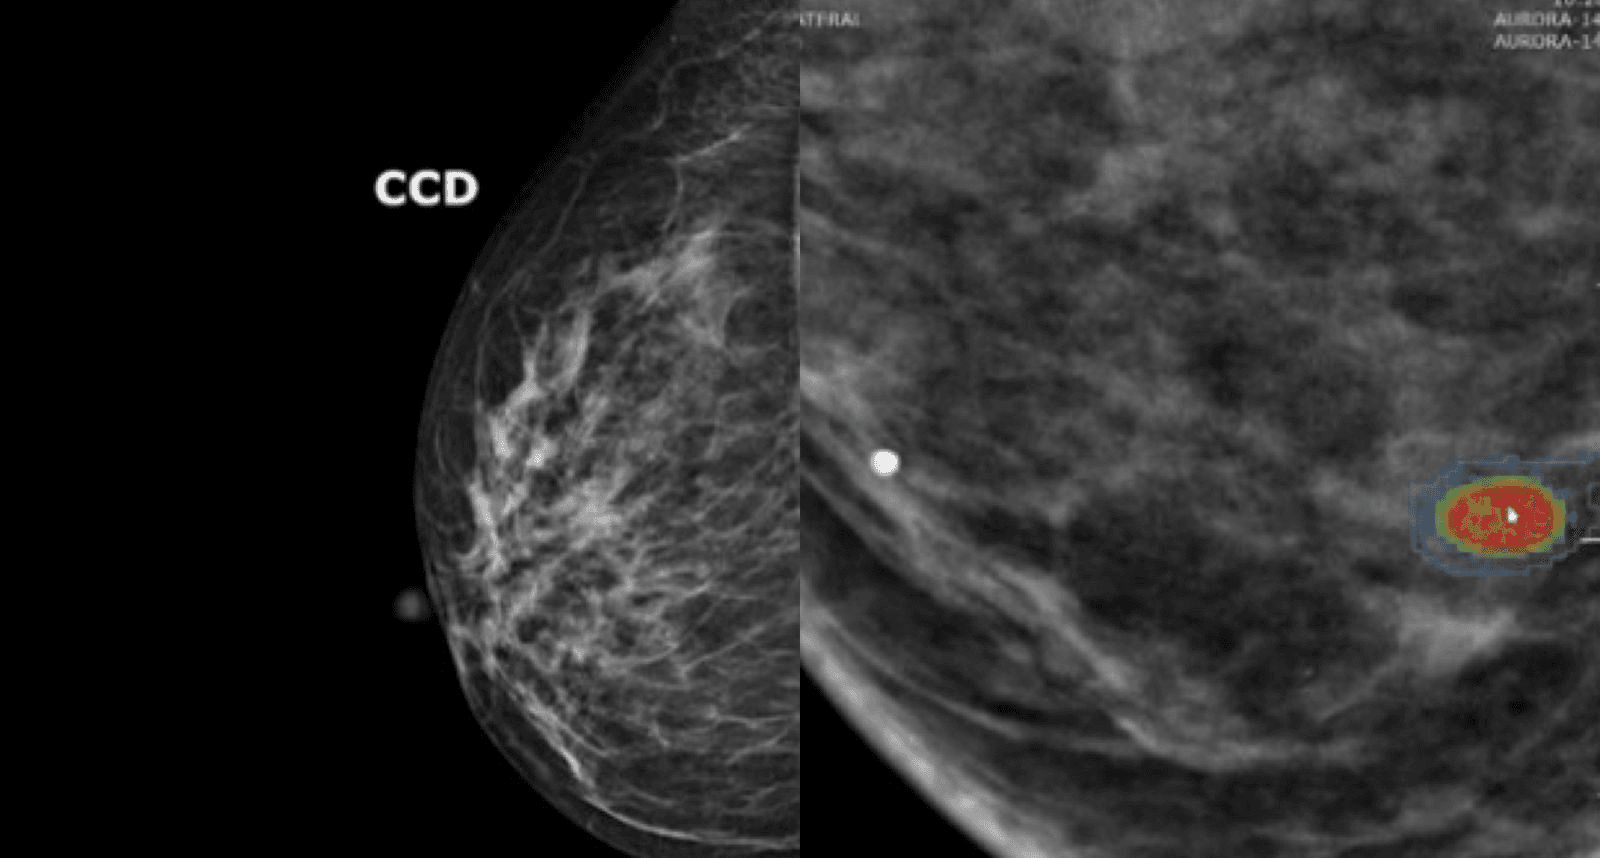

IA ajuda na triagem de mamografias em SC, acelerando diagnóstico precoce. Legenda da imagem. Reprodução: Retorno do item 11

Santa Catarina se tornou um exemplo no uso de inteligência artificial para deteção precoce do câncer de mama, condição que afeta 74 a cada 100 mil mulheres no estado, de acordo com o Instituto Nacional de Câncer (Inca). À medida que a tecnologia avança, cerca de 18 cidades do estado adotaram novas ferramentas que auxiliam no diagnóstico, tornando-o mais rápido e preciso.

As mamografias são catalisadoras dessa transformação. A médica radiologista Bianca Miranda Lago, atuando em Joinville, destaca que sua clínica realiza mais de 6 mil mamografias anuais com a ajuda da tecnologia de IA. Embora a inteligência artificial acelere a análise em até 70%, médicos permanecem responsáveis pela interpretação final dos resultados. "Levamos cerca de 30 minutos por exame, mas isso pode variar conforme o tipo de mama da paciente," explicou a especialista.

Através da análise de laudos, a ferramenta de IA identifica nódulos e sinais de alerta em tempo recorde, priorizando exames que possam indicar lesões ou microcalcificações suspeitas. A especialista em tecnologia médica, Paula Castilho, afirma que isso garante que casos mais críticos recebam atenção imediata. "A IA já detecta antecipadamente exames com lesões que exigem avaliação prioritária," revela.